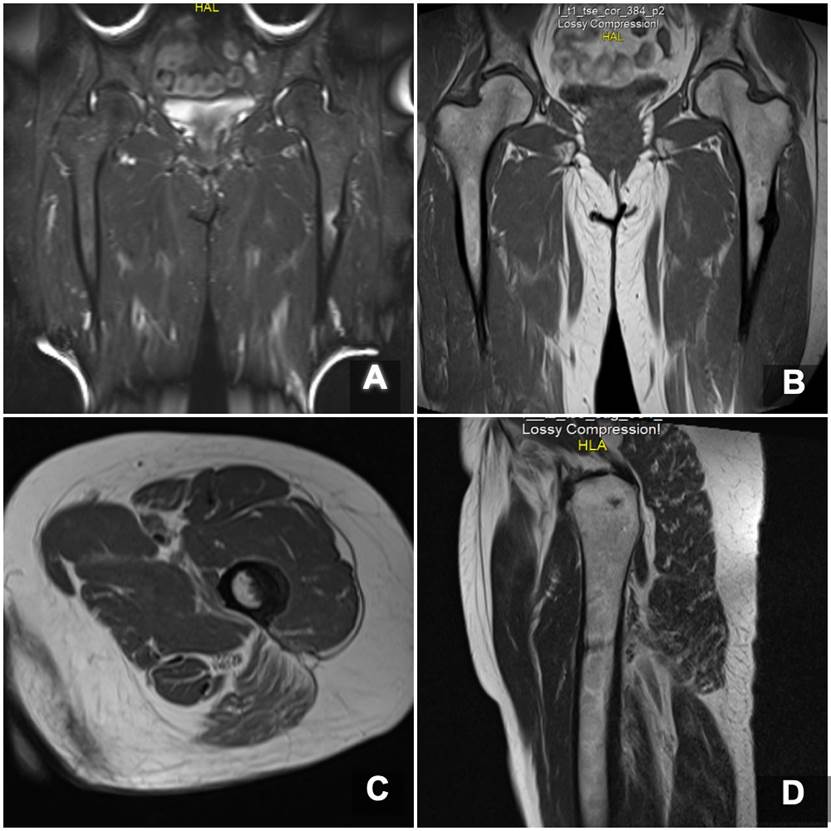

Ante estos hallazgos de imágenes, la paciente suspendió el uso de alendronato. En las imágenes de resonancia se confirma un trazo de fractura transverso no desplazado a nivel de la región subtrocantérica de fémur izquierdo en la zona del dolor (Figura 3).

Imagen de resonancia magnética en cortes coronales con secuencia STIR (A) y secuencia T2 (B), e imágenes en cortes axiales en secuencia T2 (C) y sagitales (D), donde se evidencia un engrosamiento del periostio en la cortical lateral de la región subtrocantérica de fémur izquierdo, a partir de la cual se origina un trazo de fractura incompleto en sentido transverso hacia la cortical medial.

Figura 3: Imagen de resonancia magnética en cortes coronales con secuencia STIR (A) y secuencia T2 (B), e imágenes en cortes axiales en secuencia T2 (C) y sagitales (D), donde se evidencia un engrosamiento del periostio en la cortical lateral de la región subtrocantérica de fémur izquierdo, a partir de la cual se origina un trazo de fractura incompleto en sentido transverso hacia la cortical medial.

Fuente: los autores.